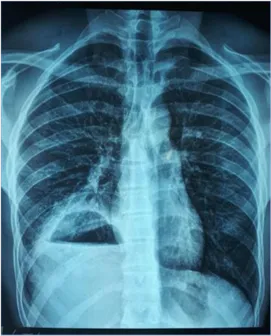

Observation 2Ms. N.H, 59 years old, with no specific pathological history, had consulted for low abundance hemoptysis, hydatydoptysis and right basithoracic pain. The general condition was good and the clinical examination had ound a right basithoracic matity and a sensitivity of the right hypochondrium. The chest X-ray had objectified an aspect of ascent of the right diaphragmatic dome. Hydatic serology was positive at 1/1320 in IHA, and there were no extra thoracic localizations. The thoracic-abdominal scanner had shown a cystic image of the multivesicular hepatic dome, seat of calcifications, and measuring 110/90 mm with a condensation of right lower lobar pulmonary (Fig-3).

Fig-3: Thoraco-abdominal CT (a: cross section, b: ) showing a cystic image of the hepatic dome measuring 110/90 mm multivesicular seat of calcifications (arrows)